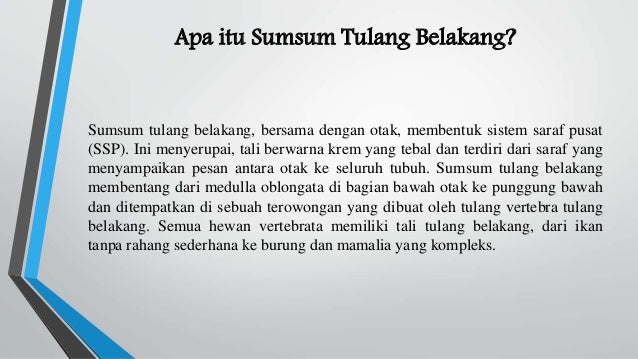

Sumsum Tulang Belakang Pengertian Letak Fungsi Struktur Dan Bagian Struktur Sumsum Tulang Belakang Medula Spinalis Manusia Lengkap

Sumsum Tulang Belakang Pengertian Letak Fungsi Struktur Dan Bagian Struktur Sumsum Tulang Belakang Medula Spinalis Manusia Lengkap